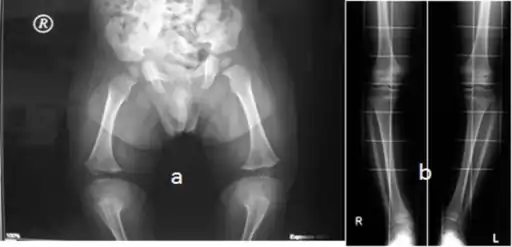

Skeletal survey in favor of hypochondroplasia -

a,b)10 year old with hypochondroplasia (with variable degrees of genu varum)